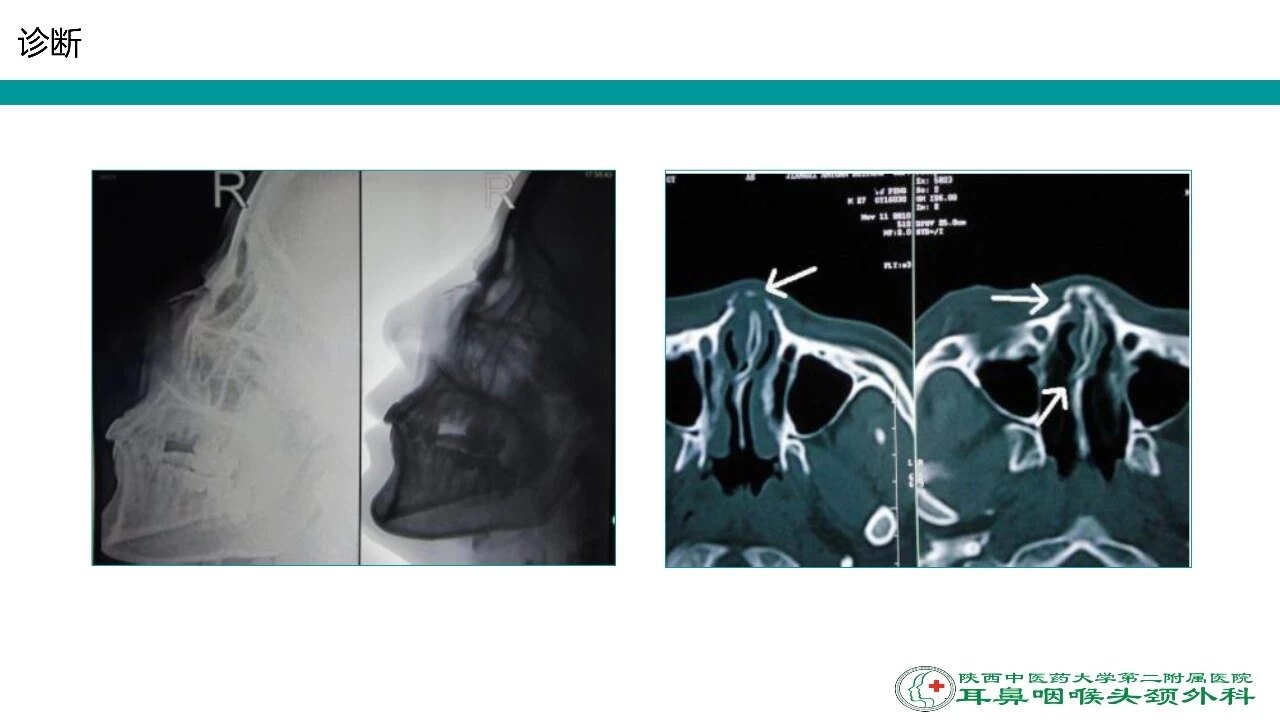

鼻骨骨折または軟骨の損傷は,腫脹,圧痛点,過可動性,crepitus(捻髪音),鼻出血,および眼窩周囲の皮下出血を来すことがある。 診断は通常臨床的に行う。 治療には,整復法,内部のパッキングによる安定化,副子固定などがある。 鼻中隔血腫は 鼻骨骨折は顔面骨骨折のなかで最も発生頻度が高く, 救急センターを併設している当院では日常診療のなかで しばしば経験する疾患である 鼻骨骨折の症状としては, 外鼻変形や鼻出血, 鼻閉が主であるが, 初診時には鼻背Class II 鼻骨と鼻中隔の他に、周辺の骨の骨折があり、粉砕骨折となっている。